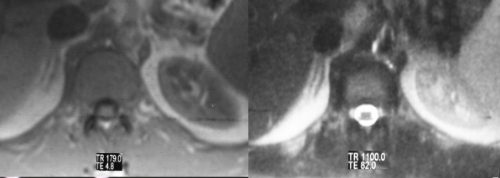

Because the normal adrenal gland is surrounded by retroperitoneal fat, the relatively low intensity of the gland is seen in sharp contrast to the fat, particularly on T1 weighted images. MRI is best used in the characterization of adrenal gland masses.The T1-weighted sequence is performed to optimize the morphology of the gland and the “in-phase” and “out-of-phase” techniques are also useful in defining the incidentaloma. The T2-weighted sequence enables the characterization of lesions with high water content as well as pheochromocytomas. |

These images reflect a normal right adrenal gland showing the difference between the normal T1-weighted and T-2weighted images. On T1-weighted images, (first figure) the intensity of the adrenals is almost isointense with the liver, while on T2-weighted image, (second figure) the adrenal is brighter than the liver. Courtesy of: Ashley Davidoff, M.D. |

The above images are fat suppressed T1-weighted fat suppressed images of the right adrenal gland. Note the progressive and rapid gadolinium enhancement of the right adrenal gland. In this case, the adrenal gland enhances to the same extent as the spleen and slightly less than the kidneys. Courtesy of: Ashley Davidoff, M.D. |